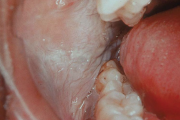

Kontaktist tekitatud kahjustused suulimaskestal

-Kontaktist põhjustatud mehhaanilist limaskesta kahjustust võivad esile kutsuda ortodontilised plaadid, breketid Harva põhjustavad kahjustusi täidismaterjalid.- Metalliärritust võivad anda breketid, aparaatide klambrid, hambakroonid – kroom, nikkel, berüllium, palladium, kloriid. Siia Loe edasi »